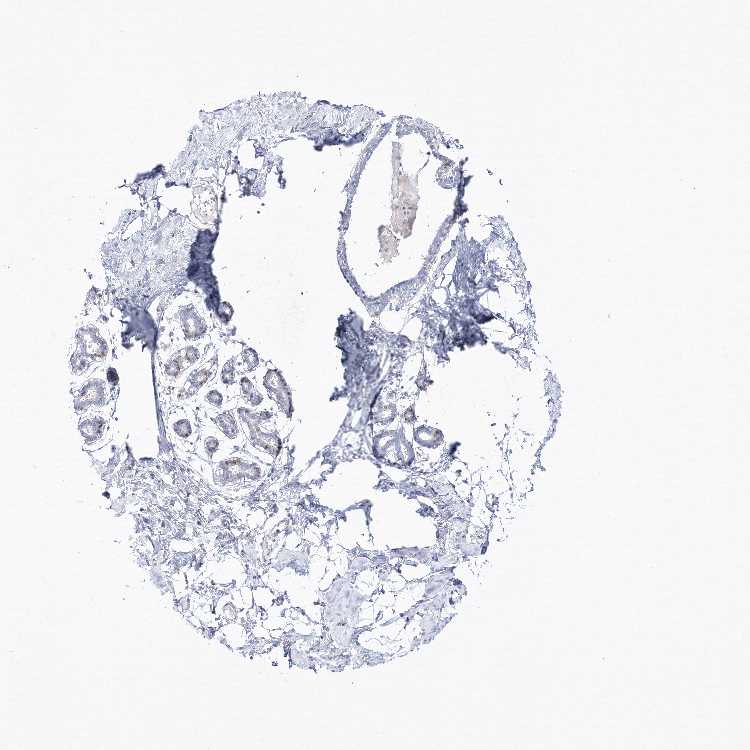

BREAST - Antibody stainingi

Antibody staining in the annotated cell types in the current human tissue is reported as not detected, low, medium, or high, based on conventional immunohistochemistry profiling in selected tissues. This score is based on the combination of the staining intensity and fraction of stained cells.

Each image is clickable and will lead to virtual microscopy that enables deeper exploration of all samples and also displays staining intensity scores, fraction scores and subcellular localization as well as patient and tissue information for each sample.

Antibody HPA037473Antibody HPA037474

Adipocytes Not detectedLow

Glandular cells LowMedium

Myoepithelial cells Not detectedNot detected